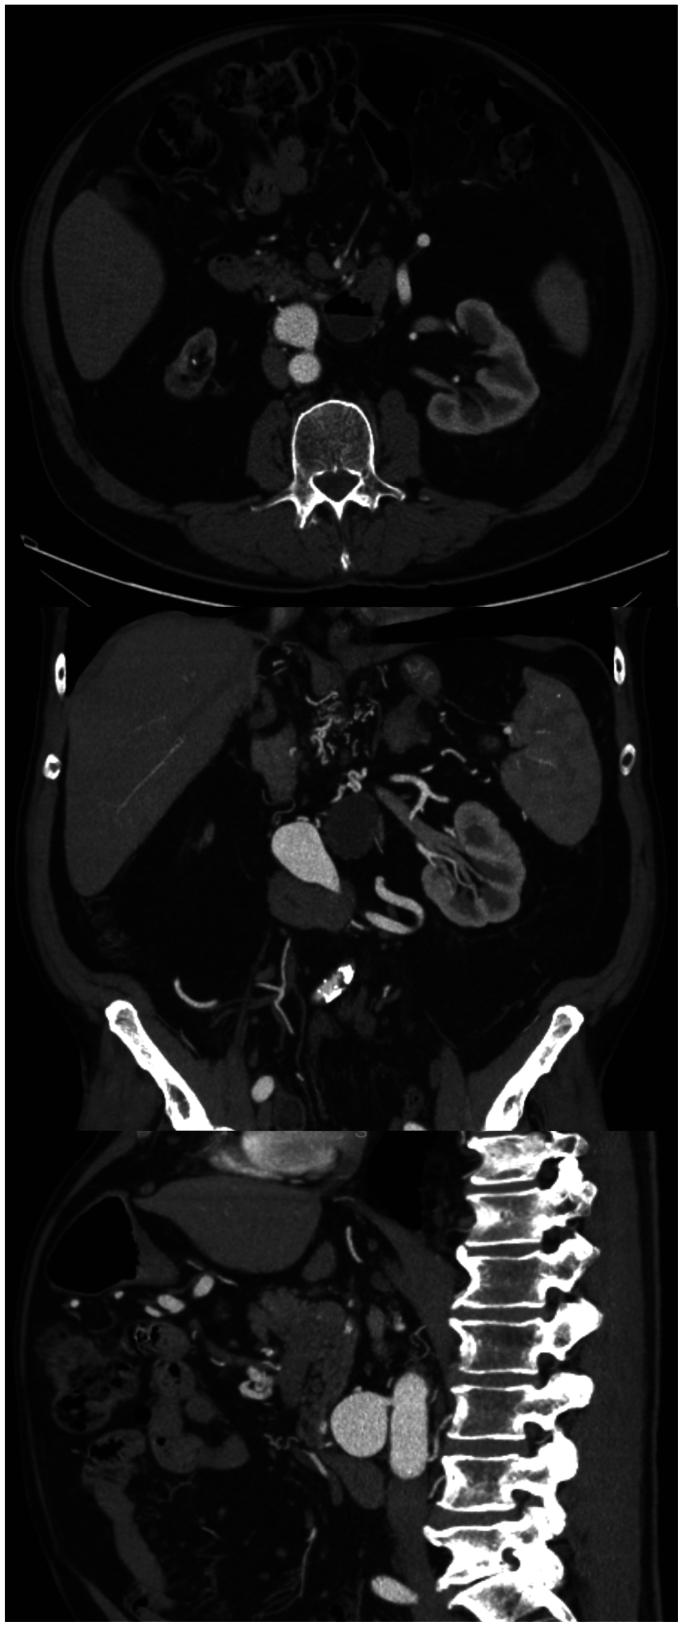

Inferior mesenteric artery (IMA) aneurysms account for approximately 1% of visceral artery aneurysms and can occur secondary to high flow because of occlusive disease in other mesenteric arteries. We describe the case of a 79-year-old man who presented with a 3.3-cm IMA aneurysm and chronic total occlusions of the celiac artery and superior mesenteric artery (SMA). After an unsuccessful attempt at endovascular SMA recanalization, he underwent an uncomplicated retrograde aorta to SMA bypass and antegrade aorta to IMA bypass. We propose that an aorta to IMA bypass after SMA revascularization is safe and effective to treat suspected high-flow IMA aneurysms.